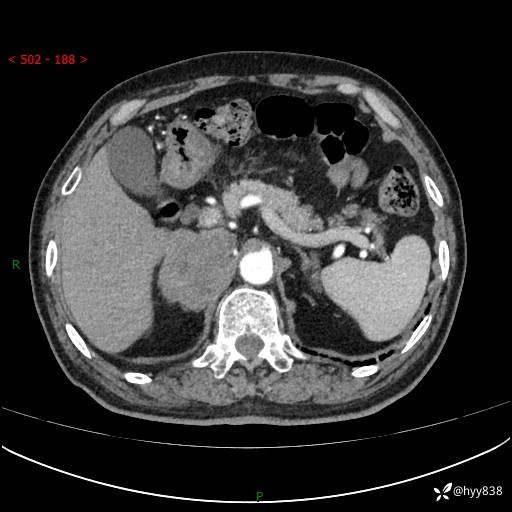

【患者信息】:76岁/男

【主诉】:检查发现右侧肾上腺占位6天

【现病史及既往史】:患者6天前体检发现右侧肾上腺占位,无腰痛,无放射痛,无尿频、尿急、尿痛及肉眼血尿,无畏寒、发热,无恶心、呕吐,今为求进一步治疗,遂来我院就诊,门诊拟“右侧肾上腺占位”收住入院。 起病以来,患者精神、饮食、睡眠可,大小便如常,体力体重无明显变化。

【检查】:肾上腺CT平扫+增强